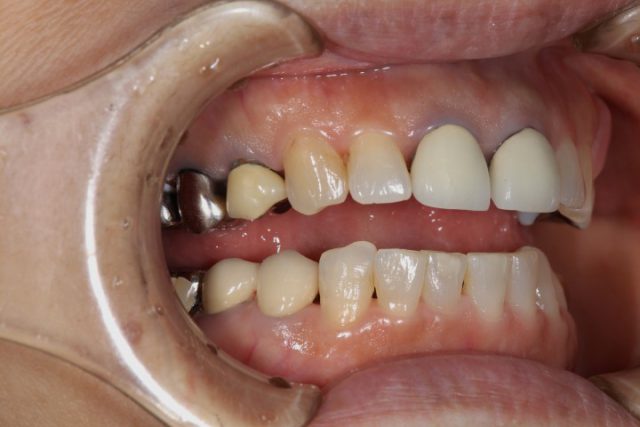

施術前

過去に歯が折れてしまい被せ物をされていたのですが、歯と歯の間に隙間ができてしまい年々空いてくるという状態でした。また、周りの歯とも色が合っていないのが気になっておられたことから今回オールセラミックによる施術されることになりました。

術前の画像から上前歯2本に隙間ができていることがわかります。また、被せ物の付け根も黒ずんでいるのが分かります。